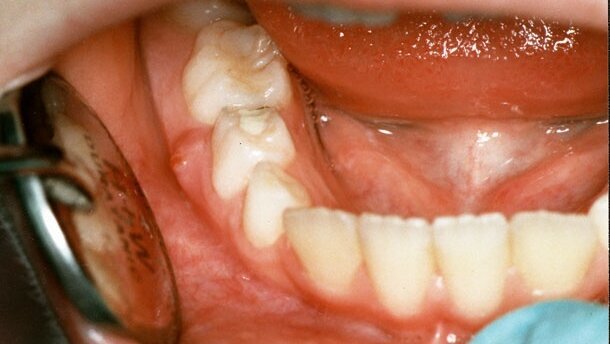

Patientenfall 2: Alter der Patientin: 13 Jahre; 11. April 1995: Gangrän an 84 mit Fistel.

Abb. 1-2, v. l. n. r.: 84 vor Mortalamputation am 11.4.1995, 84 nach Mortalamputation am 11.4.1995.

Abb. 3-5, v. l. n. r.: 11.4.1995: 84 Fistel vor Behandlung; Starke Blutung der Pulpa; 84 Kavität vollständig mit N2 aufgefüllt; 17.4.1995: Fistel verschwunden. N2 z.T. aus Kavität gekratzt zwecks Füllung (nach Angaben der Mutter sei die Fistel bereits 1 Tag nach Mortalamputation verschwunden).